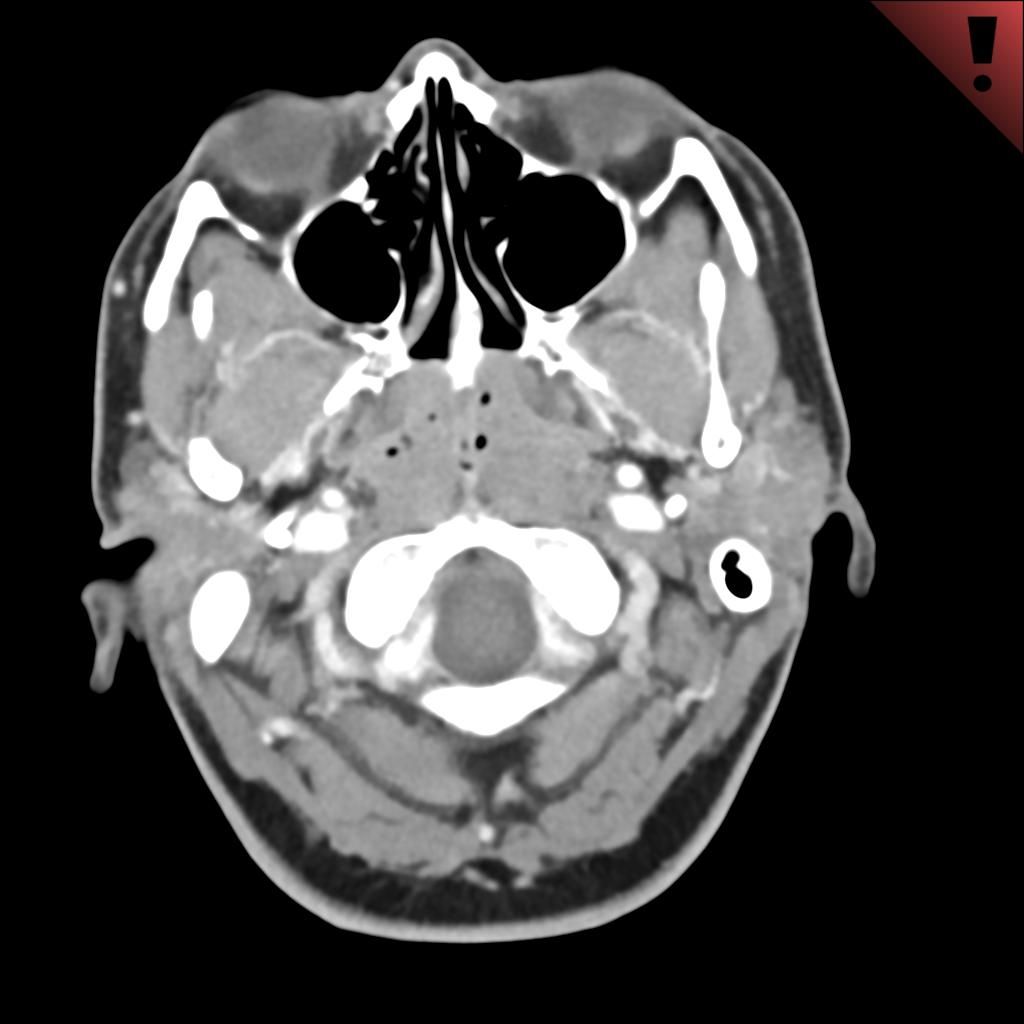

Case History: 60-year-old female presented with complaint of swelling of left mandible.